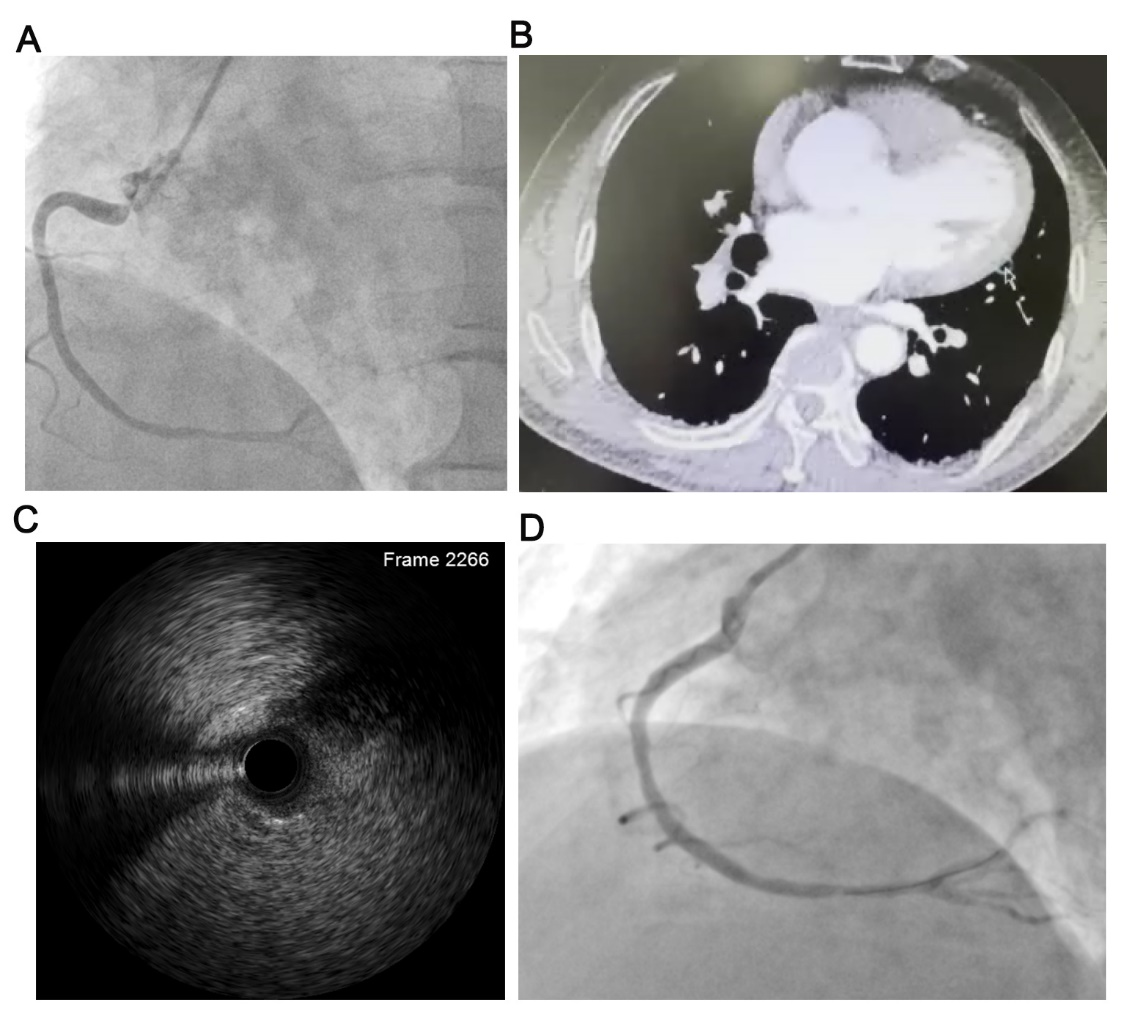

当时50多岁的符某某因持续胸痛来湘雅二医院急诊就诊,结合心电图提示为急性下壁心梗,医院胸痛中心快速反应,启动导管室进行急诊冠状动脉造影时发现升主动脉扩张、主动脉瓣返流,且难以找到右冠状动脉开口,急诊术者怀疑升主动脉夹层遂急诊行主动脉CTA检查,检查结果提示未见明确主动脉夹层。由于患者持续胸痛,便迅速再次返回导管室并尝试各种方法终于找到了右冠状动脉开口,造影提示开口严重狭窄,远端血流不佳,建立导丝轨道后行血管内超声检查,除了发现少量斑块外还可见右冠开口有明显受压迫表现,但并未见到斑块破裂及血栓征象。为保障血流,于右冠开口成功植入一枚支架。患者回病房后出现发热、心衰加重,并发生急性脑梗,心脏超声示主动脉瓣返流加重同时提示瓣膜表面赘生物可能,瞬间,感染性心内膜炎又成了MTD团队的专家们必须考虑的诊断,然而尽管CT检查未能发现主动脉夹层,但这诊断始终在专家们心中挥之不去!

图2. 多重影像手段确认右冠开口受压